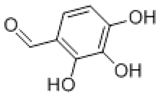

产品名称:2,3,4-三羟基苯甲醛

别名:邻苯三酚-4-甲醛

CAS No.: 2144-08-03

分子式:C7H6O4

分子量:154.12

结构式: